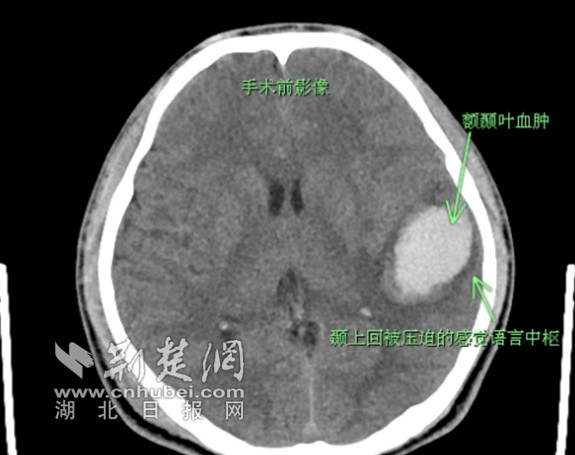

在充分了解到小余发病的具体经过并进行相关检查后,医生们发现小余的出血部位在左侧额颞叶,出血量已超过30ml,且正好影响到了语言中枢,如不及时手术,小余不仅语言功能可能无法恢复,随着脑水肿加重,还可能引起严重脑疝从而危及生命。由于小余年纪较小,除了挽救功能以外,还需要考虑伤口的瘢痕增生、头发生长等美观问题,武汉市普仁医院神经外科二病区主任潘德锐立即为小余制定了相关手术治疗方案,决定采用微创小骨窗的形式清除血肿。

小余的脑内血肿清晰可见 通讯员供图